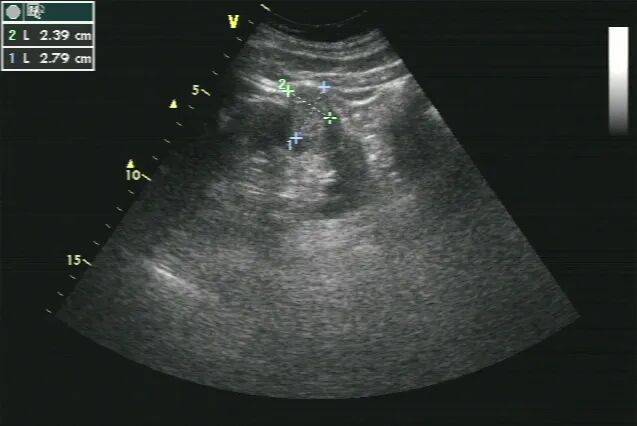

1. 左肾形态失常,体积增大,内部结构紊乱,呈混合性回声,以实性为主,内部可见不规则无回声。CDFI:混合性回声内部及周边未见明显血流信号(图 1、2)。

图 1 灰阶超声示肾癌超声表现( LK 左肾)

图 2 彩色多普勒超声示内部未见血流信号( LK 左肾)